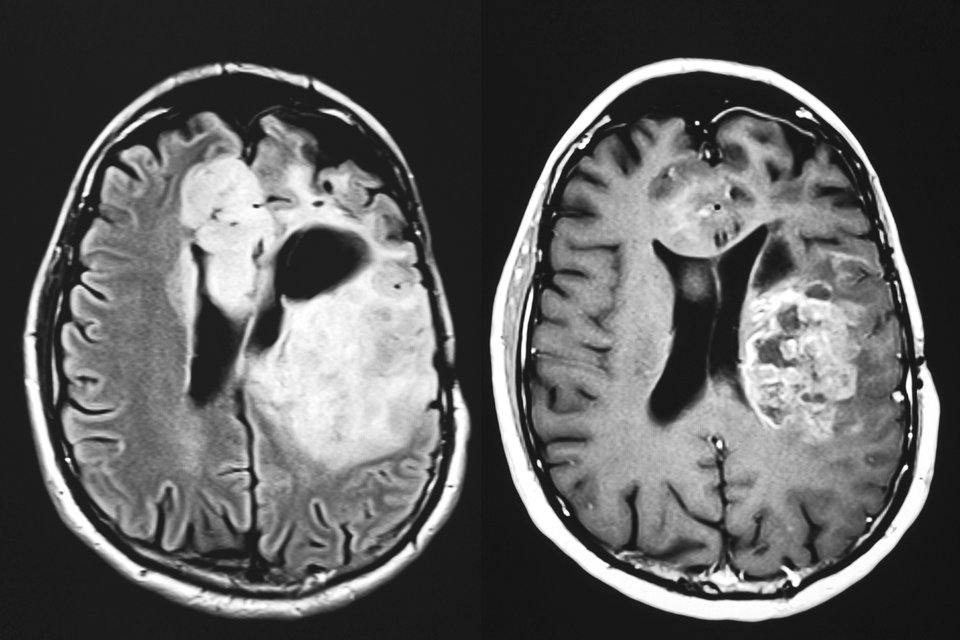

Ein sekundärer ZNS-Befall durch B-Zell-Lymphome war bislang eine Komplikation mit sehr schlechter Prognose. Neue therapeutische Strategien machen nun Hoffnung auf eine deutliche Verlängerung der Überlebenszeit.

Bis vor Kurzem lag die mediane Überlebenszeit für Patienten mit sekundären ZNS-Lymphomen bei lediglich etwa zehn Monaten.

Nach drei Jahren war noch ungefähr jeder Fünfte am Leben und selbst wenn die Patienten eine Hochdosistherapie mit autologer Stammzelltransplantation erhalten konnten, waren es kaum viel mehr als 40 %.